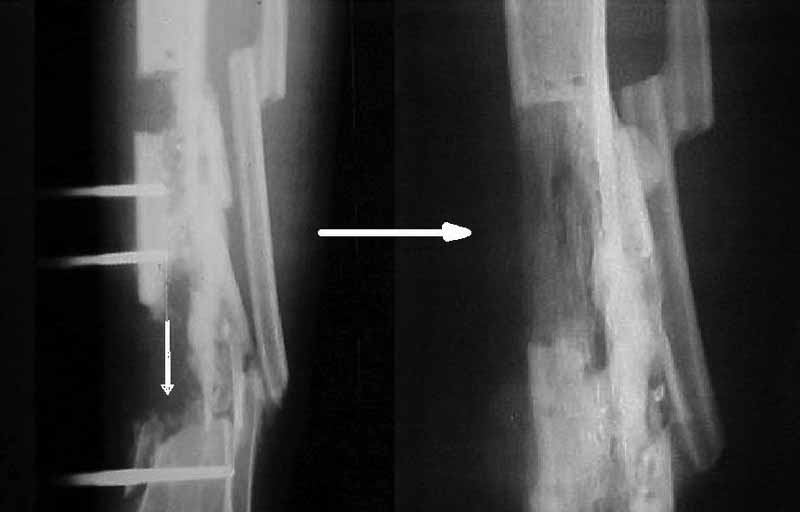

Я бы сделал пластику мягких тканей (торакодорзальный лоскут совместно с микрохирургами или пластику латеральной головкой икроножной мышцы) и выполнил бы краевой отщеп большеберцовой кости для его дистракции аппаратом в проксимальном направлении (рис. 1 – пример применения отщепа (авторство не мое), рис. 2 – схема предлагаемого варианта замещения дефекта кости).

Можно ведь и расщепленный фрагмент малоберцовой кости внедрить в дефект по Илизарову.Почему нет?Тогда сохранится и малоберцовая кость и заполнится дефект.Возможно и пластик никаких не потребуется,да и дремлющая инфекция не так страшна.

5. Если решать проблему замещения костного дефекта, то предложенный Павлом Ивановым вариант - наиболее реальный из известных, хотя и весьма сложный.

6. Готов предложить нестандартное решение в этой нестандартной ситуации. Межберцовое синостозирование в проксимальном отделе - между

головкой малоберцовой кости и наружным мыщелком. Это создаст дополнительную опору, которой может оказаться достаточно для функционирования.